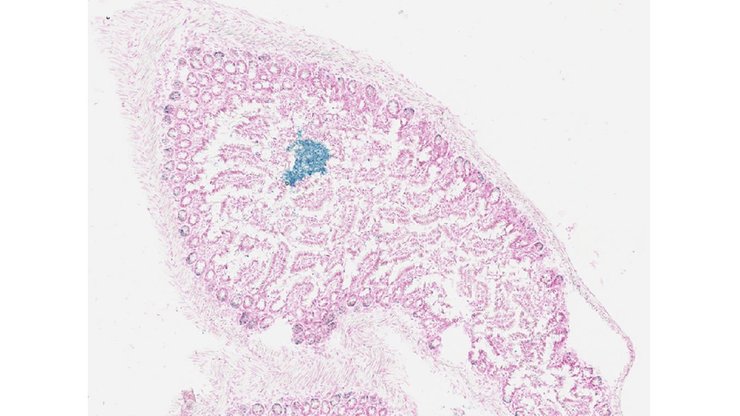

Specimen UC Davis_1862878: postnatal adult; Ctdspltm1.1(KOMP)Mbp/Ctdspl+ (more )

Structure Level Pattern Image Note

TS28: ovary Present UC Davis_1862878